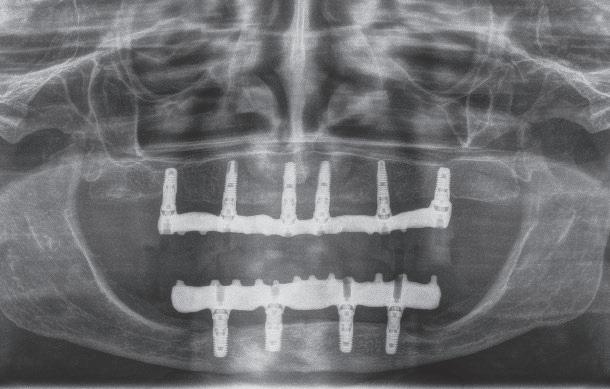

SFIG. 4, a-e. Fracturas múltiples complejas mandibulares y un caso de fractura condilar baja y abordaje retroparotideo. a) Control con OPG un año después de una fractura panfacial por accidente de tráfico afectando a la órbita, al maxilar superior y a la mandíbula. La osteosíntesis en estos casos siempre se comienza desde craneal a caudal. Se observa la osteosíntesis necesaria (tres microplacas y una miniplaca de titanio, así como un alambre en la parasinfisaria izquierda) para estabilizar la fractura conminuta condilar y de rama ascendente mandibular derecha, que se logró mediante abordaje combinado retromandibular e intraoral. b) Mujer de 24 años con fractura condilar baja (tipo II de Spiessl) izquierda que requirió abordaje abierto; se confirma en la TC-3D desplazamiento del fragmento condilar hacia medial (C) y lateralidad de la línea de fractura (flechas rojas). b) Diseño del abordaje retromandibular izquierdo de 2 cm bajo la inserción del lóbulo de la oreja, antes de la infiltración prequirúrgica. c) Imagen intraoperatoria del abordaje tras reducción y osteosíntesis con una miniplaca de 4 tornillos recta de titanio. d) Control inmediato posoperatorio con OPG donde se observa la correcta reducción de la fractura con la miniplaca (círculo rojo) y se objetiva además un mucocele inflamatorio en el seno maxilar izquierdo (flechas amarillas) posiblemente provocado por el tercer molar superior izquierdo (28).